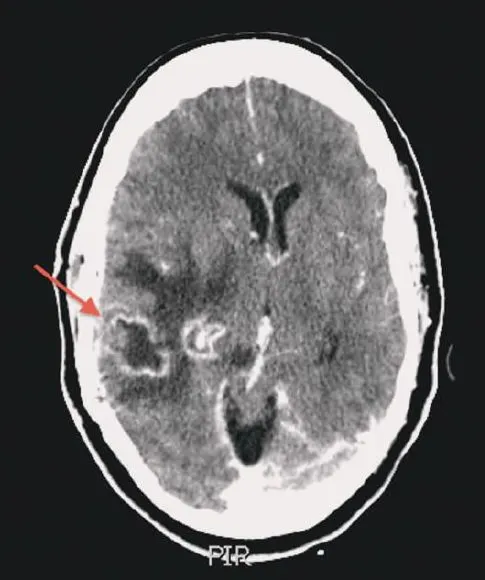

(1) Contrast CT – 조영증강된 ring shape 외피, 안으로 low density, 주변 brain의 edema